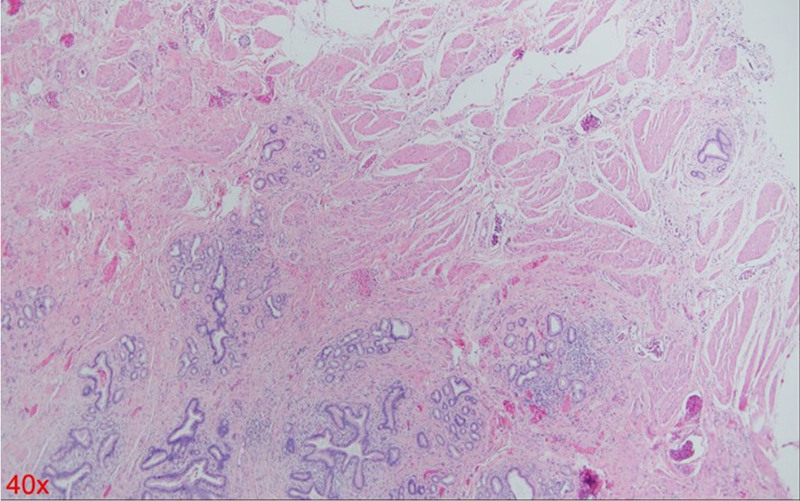

A 54-year-old woman with a medical history of hypertension and hyperlipidemia presented to the outpatient department complaining of persistent epigastric dull pain. Abdominal ultrasonography revealed significant dilation of the CBD (up to 15.2 mm); however, no obvious intraductal mass, bile duct wall thickening, CBD stones, or pancreatic head tumors were identified (Fig. 1). Subsequent abdominal CT demonstrated a contrast-enhanced tumor-like mass measuring approximately 1.6 cm in the distal CBD, characterized by wall thickening without distinct intraductal lesions. Magnetic resonance imaging (MRI) confirmed narrowing of the distal CBD with mild upstream dilatation measuring 10.9 mm, without liver, pancreatic, or lymph node involvement (Fig. 2). Physical examination of the abdomen revealed no tenderness, and the patient denied experiencing fever, nausea, vomiting, or loss of appetite. Laboratory investigations revealed an elevated level of γ-glutamyl transferase (GGT) at 130 U/L, while regular blood tests, as well as levels of carcinoembryonic antigen (CEA), cancer antigen 153 (CA153), and CA199, were within normal ranges (Table 1). Suspecting a bile duct tumor, a Whipple procedure was performed for both diagnostic and definitive treatment purposes (Fig. 3). Histological examination of CBD sections revealed adenomyomatous hyperplasia characterized by clusters of benign biliary glands embedded within fibromuscular stroma and surrounded by lymphoplasmacytic inflammatory cells (Fig. 4). The lesion exhibited no signs of malignancy, confirming its benign nature. The patient experienced a satisfactory recovery and was discharged 19 days post-surgery.

In this patient’s case, preoperative imaging clearly identified a tumor, and both CT and MRI scans strongly suggested cancer. The primary finding was significant wall thickening of the bile duct without a large mass formation. Consequently, ERCP biopsy would likely have difficulty capturing the tumor tissue, potentially leading to a false-negative report of benign changes. Regardless of the biopsy result, surgery would still be necessary due to the high suspicion of malignancy based on imaging findings. Therefore, this patient did not undergo preoperative ERCP. If the patient had undergone ERCP with tissue sampling from the correct location, the histological findings would likely resemble those shown in Figure 4, demonstrating adenomatous hyperplasia. This scenario would present a clinical dilemma, where imaging suggests a tumor suspicious for cancer, but the biopsy indicates a benign process